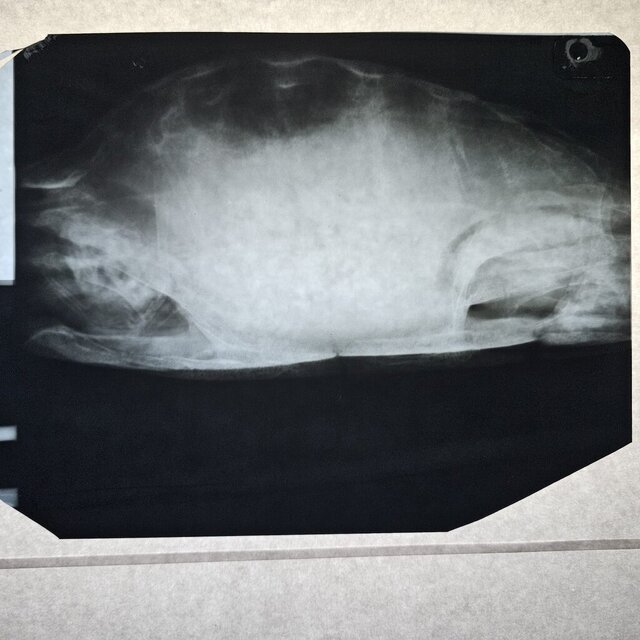

Добрый день. Сходили в клинику Степаненко в Харькове, но приём вела не она. Сдали кровь её удалось взять очень мало. Сделали ренген. Получили назначения. Там нам вкололи Элеовит. Сказали что все очень плохо. Анализ крови скину завтра клиника не прислала

Назначения из клиники